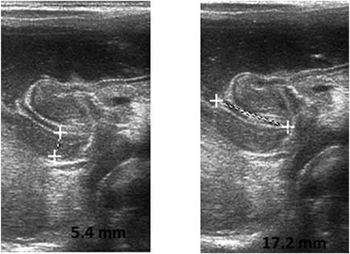

Case history: A 4-week-old male neonate was brought with the complaints of vomiting after feeds for the past two weeks. It was projectile, nonbilious vomiting, progressively increasing in severity.